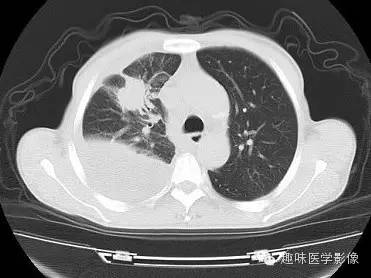

CT: 右侧胸廓缩小。右肺上叶前段结节,略分叶,可见长短不一毛刺,胸膜牵拉征及血管集束征,右肺组织向肺门萎陷,左肺清晰,未见异常。纵隔内见淋巴结肿大(4R淋巴结增大)。右侧前壁及侧后胸壁包裹性积液征象。

右上肺周围型肺癌,纵隔淋巴结转移,胸膜腔包裹性积液。